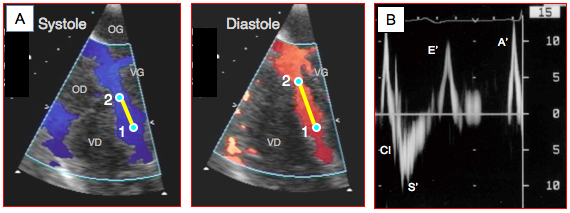

Figure 25.28 : Déformation tissulaire. A: vélocité de déplacement du tissu myocardique dans le VG au cours d'un cycle cardiaque; la Vmax est de 10-12 cm/s (voir aussi Figure 25.29B). B: déformation tissulaire (strain); la systole est une déformation négative (raccourcissement) et la diastole une déformation positive. C: vitesse de la déformation (strain rate); elle varie avec les phases du cycle cardiaque. CI: contraction isovolumétrique. S': systole mécanique. E': relaxation protodiastolique. A': contraction auticulaire. Le trait violet représente l'accélération de la contraction isovolumétrique (Vmax/Δt). Δt: durée de la CI. Amplitude: valeur de la Vmax de la CI [12].

Figure 25.29 : Doppler tissulaire (DT). A : affichage couleur des mouvements du septum interventriculaire en vue 4-cavités 0°. La descente de l'anneau mitral en systole se traduit par une vélocité de déplacement longitudinal illustrée par une coloration bleue (éloignement du capteur); le mouvement inverse a lieu en diastole (couleur rouge). Le DT mesure la vélocité des deux points situés à l'extrémité du segment sélectionné (V1 et V2). B : affichage Doppler spectral de la vélocité du mouvement de l’anneau mitral (échelle de vélocité 15 cm/s). CI : contraction isovolumétrique. S' : éjection systolique (descente de l’anneau mitral dû à la contraction longitudinale), Vmax 10-15 cm/s. CI: contraction isovolumétrique. E’ : mouvement de l’anneau mitral en relation avec la relaxation protodiastolique. A’ : mouvement de l’anneau mitral en relation avec la contraction auriculaire.